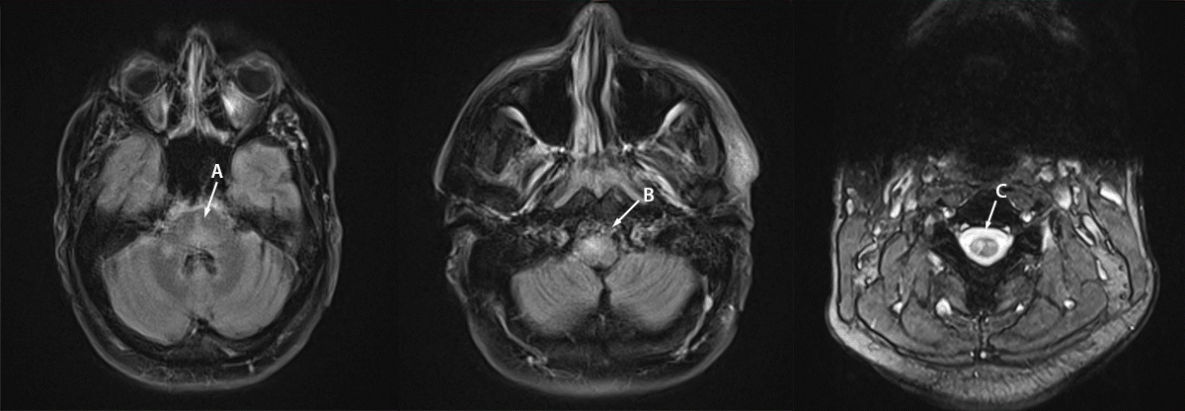

The second case of MPXV-associated encephalomyelitis occurred in a previously healthy, presumedly immunocompetent gay man in his 30s in DC (patient B). He had no known MPXV exposure or recent travel. He had not been vaccinated against monkeypox and his smallpox vaccination status was uncertain. In July 2022, he acutely developed fever and myalgia, which was followed by eruption of a diffuse vesiculopustular rash involving his face, extremities, trunk, and perianal area. Swabs of a lesion yielded positive Orthopoxvirus DNA PCR test results, later confirmed to be MPXV DNA. Five days after symptom onset, he developed bowel and bladder incontinence and progressive flaccid weakness of both lower extremities and was hospitalized. His condition progressed to altered mental status and obtundation during the next 2 days. He was intubated for airway protection and transferred to the intensive care unit. MRI of the brain showed nonenhancing lesions of the pons, cerebellum, and medulla without restricted diffusion (Figure 2). MRI of the spine showed multifocal, partially enhancing lesions in the central cervical and upper thoracic regions (Figure 2). Computed tomography imaging of the abdomen and pelvis demonstrated rectal thickening with pelvic lymphadenopathy consistent with proctitis, thought to be related to MPXV infection. CSF analysis demonstrated 30 white blood cells/μL with 89% lymphocytes and 11% monocytes; 4 red blood cells/μL, glucose 65 mg/dL, and protein 60 mg/dL. CSF bacterial cultures and CSF HSV and VZV PCR results were negative. Three CSF-specific oligoclonal bands were present. Serum and CSF aquaporin-4 and MOG antibody test results were negative. Serum HIV serologic and PCR test results were negative, as were serum RPR and CSF VDRL test results and rectal and urine gonorrhea and chlamydia screening results. SARS-CoV-2 reverse transcription–PCR nasopharyngeal swab test result was negative at admission and when febrile. CSF MPXV PCR test result was negative.

FIGURE 2. Magnetic resonance imaging of the brain and cervical spine of patient B with monkeypox-associated encephalomyelitis showing abnormal T2/fluid attenuated inversion recovery signal in the pons and cerebellum (A), medulla (B), and gray matter of the cervical spinal cord (C) — District of Columbia, July–August 2022

Photos/Matthew J. Copeland.